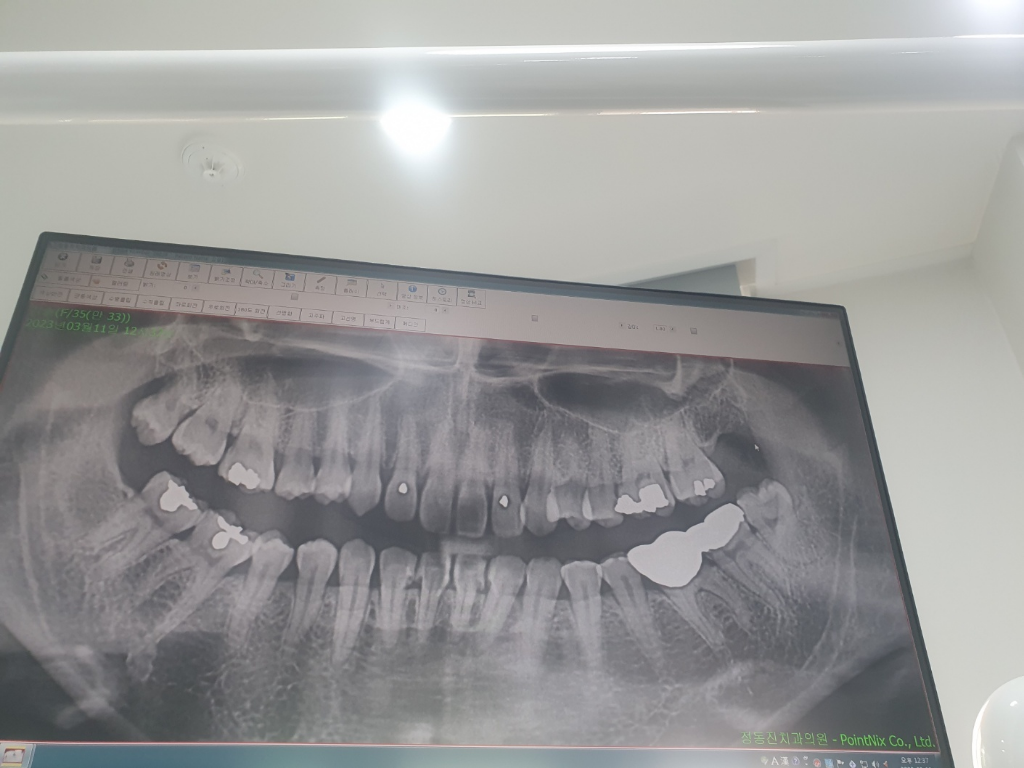

제 파노라마에서 얼마나 썩은건가요?

제 파노라마 사진인데요

제가 블로그보니 검으면 충치나 염증이라는데

앞니 윗니들이 그러면 썩은건가요?..ㄷㄷ

그리고 사랑니는 많이 썩었나요?...

전반적으로 제 치아상태나 주의할부분 파노라마 분석부탁드립니다!

까맣다고 다 충치나 염증은 아닙니다. 사랑니도 썩은 건 아닌 것 같지만 빼는 게 좋겠습니다.

엑스레이 상에서 보이는 앞니의 경우는 입술이랑 겹쳐서 저렇게 보이는겁니다. 충치가 잇는건 아닌거 같습니다. 사랑니도 크게 충치가 잇거나 하진 않아 보입니다.

파노라마상 앞니는 다른 구조물과 겹치면서 저렇게 보이고 실제로는 충치가 아닙니다

사랑니는 파노라마상에서 충치가 있어보이긴 합니다

왼쪽 아래 크라운 2개가 연결되어 있으므로 치실말고 치갼칫솔로 해당부위는 관리해주셔야 합니다